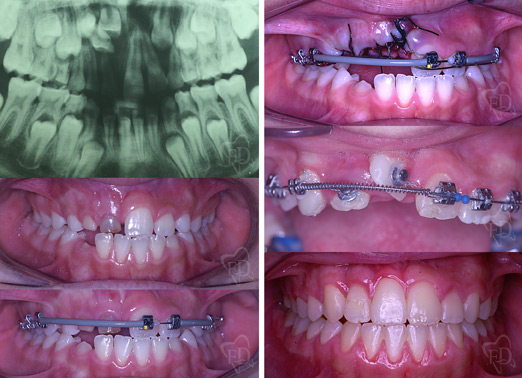

Terapia intercettiva:

prima dopo

Inclusione dentaria multipla